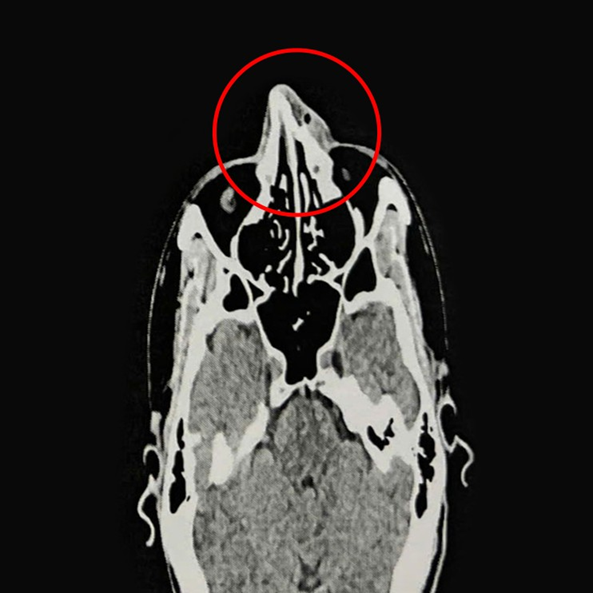

ThS.BS.CKI Nguyễn Trung Nguyên, Trung tâm Tai Mũi Họng, Bệnh viện Đa khoa Tâm Anh TP.HCM, cho biết kết quả nội soi và chụp CT 128 lát cắt ghi nhận xương mũi của anh Phi bị gãy ở vị trí tháp mũi, phù nề tụ khí mô mềm vùng mũi, lệch vách ngăn mũi, viêm mũi xuất tiết. Anh Phi được chỉ định phẫu thuật nâng xương mũi, chỉnh hình vách ngăn mũi.

Anh Phi được điều trị nội khoa ba ngày để giảm phù nề, mũi hết sưng viêm trước khi nhập viện phẫu thuật. Người bệnh được gây mê toàn thân. Qua nội soi kết hợp CT, bác sĩ Nguyên thấy mũi biến dạng, gãy di lệch tháp mũi và ngành lên xương hàm hai bên. Bác sĩ tiến hành chỉnh hình vách ngăn mũi, rạch niêm mạc vách ngăn phải bị vẹo, tách phần sụn tứ giác và phần xương vách ngăn bị vẹo, cắt bỏ phần xương, sụn vẹo. Sau đó nâng xương chính mũi và ngành lên xương hàm hai bên, chỉnh xương mũi thẳng, cân đối. Cuối cùng, bác sĩ đặt gạc meche chặt vào hốc mũi qua cửa mũi trước, cố định xương mũi đã nâng.